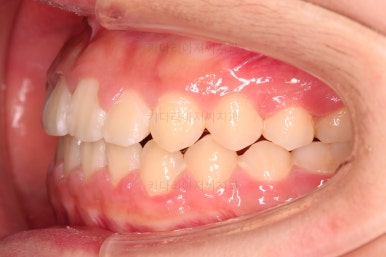

틈이 다 모였고 교합도 많이 좋아졌죠?

끝내도 될까요?

전후 사진을 비교해 볼게요.

악궁확장을 통해 위아래 악궁의 크기 조화를 맞췄고, 틈새도 모았으며 교합도 적절히 마무리를 했습니다.